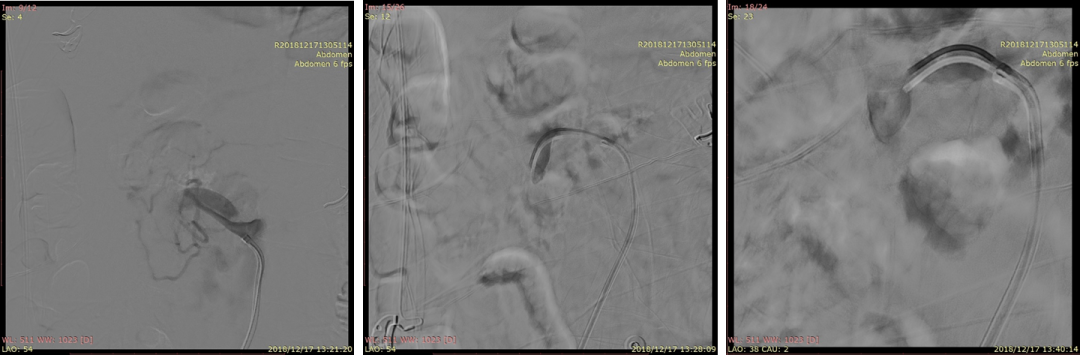

20181217DSA:破口位于距离SMA开口2cm处;破口远端真腔不显影。

20181217DSA:假腔充满血栓

20181217DSA:选择进入远端血管(回肠动脉)

20181217DSA:找到远端真腔血流受限的原因(箭头)

20181217DSA:植入第一枚支架(wallstent7*50mm)